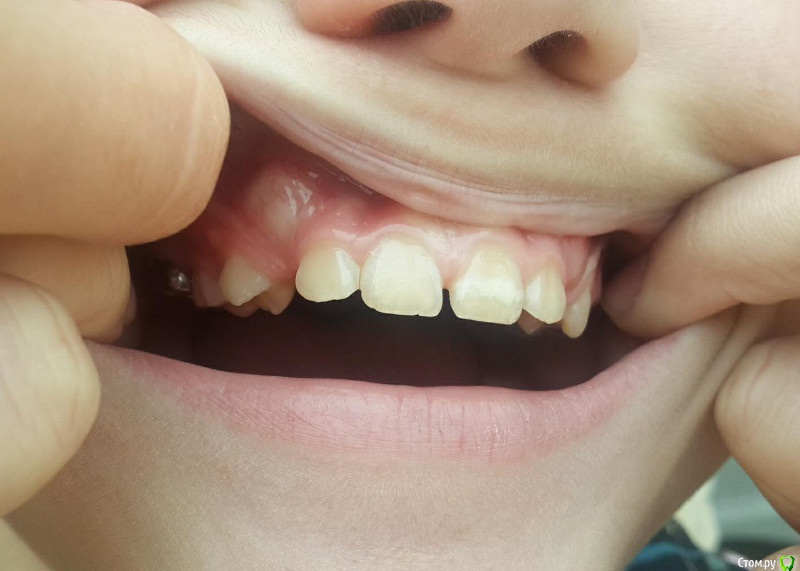

Винкс Опубликовано 22 декабря, 2017 Поделиться Опубликовано 22 декабря, 2017 Ребенок 11 лет, надо ли ждать прорезывания клыков или уже бежать к доктору. Ссылка на комментарий